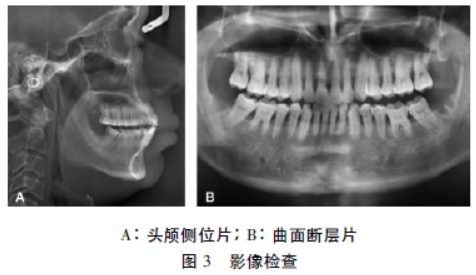

正面观面容苍老,软组织轮廓较大,眉弓突出,鼻宽唇厚,面部左右对称,长面型。侧貌为直面型(图1)。

口内检查:恒牙列,双侧磨牙近中关系,尖牙近中关系。上下切牙为切对切,尖牙反,磨牙开。下牙列中线左偏1mm。Bolton指数分析:前牙比(正常值:78.8%±1.72%:80%全牙比(正常值:91.5%±1.51%:91.6%(图2)。

模型分析:上牙列拥挤0mm,下牙列拥挤3mm;Spee曲线深约3mm。上颌:前部牙弓宽度42mm,后部牙弓宽度56mm。下颌:前部牙弓宽度44mm,后部牙弓宽度64mm。

1.3诊断

安氏Ⅲ类,骨性Ⅲ类,均角型,上前牙唇倾,下前牙唇倾(表1),上下颌牙弓宽度不匹配,前磨牙区及磨牙区开。